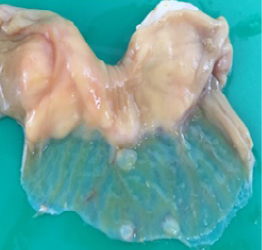

Figure 4

Transparent thinning of the intestinal wall indicative of necrotizing enteritis